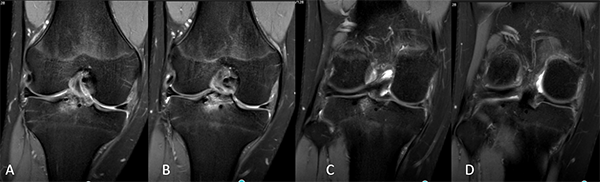

Se solicitó Rx, donde se constató fractura de espina tibial grado 3 (fig. 1), además, una tomografía axial computada (fig. 2), aportando un patrón conminuto del fragmento y RM, donde se evidenció, además de la fractura de espina tibial, una lesión en asa de balde del menisco interno (fig. 3).

Figura 2: Tomografía axial computada de rodilla derecha. Imágenes coronales que muestran la fractura de espina tibial.

Figura 3: Resonancia magnética. A-B) Cortes coronales: distensión del ligamento colateral medial, lesión en asa de balde del menisco interno, fractura avulsión de espina tibial, “bone bruise” en compartimento lateral. C-D) Cortes sagitales: avulsión de espina tibial grado 3 y tercio posterior del menisco interno flipeado hacia anterior.

El seguimiento postoperatorio comenzó con inmovilización de la rodilla por cuatro semanas con una férula inguinomaleolar, se permitieron ejercicios isométricos y de movilidad pasiva asistida 0-40° hasta la sexta semana, luego 0-90° hasta la octava semana. Al tercer mes se solicitó RM de control en la que se verificó reducción anatómica y consolidación de la fractura de espina tibial; menisco interno normoposicionado y de buena señal (figs. 7 y 8).

Figura 7: Resonancia de control. Cortes coronales, reducción anatómica y consolidación de la fractura de espina tibial. Menisco interno normoposicionado y de buena señal.

Figura 8: A) Corte sagital, LCA de buena señal, reducción de la fractura, material de fijación en espina tibial. B-C) Cortes sagital y axial. Menisco interno normoposicionado, cambios de señal vinculados a sutura meniscal.